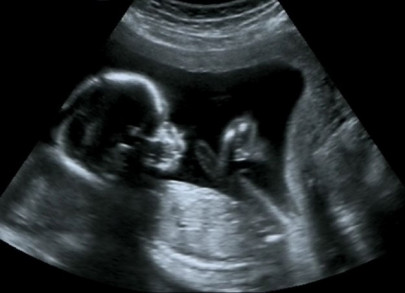

Women aged under 30 with a male partner aged 40 to 42 saw chance of live birth after IVF fall to 46%